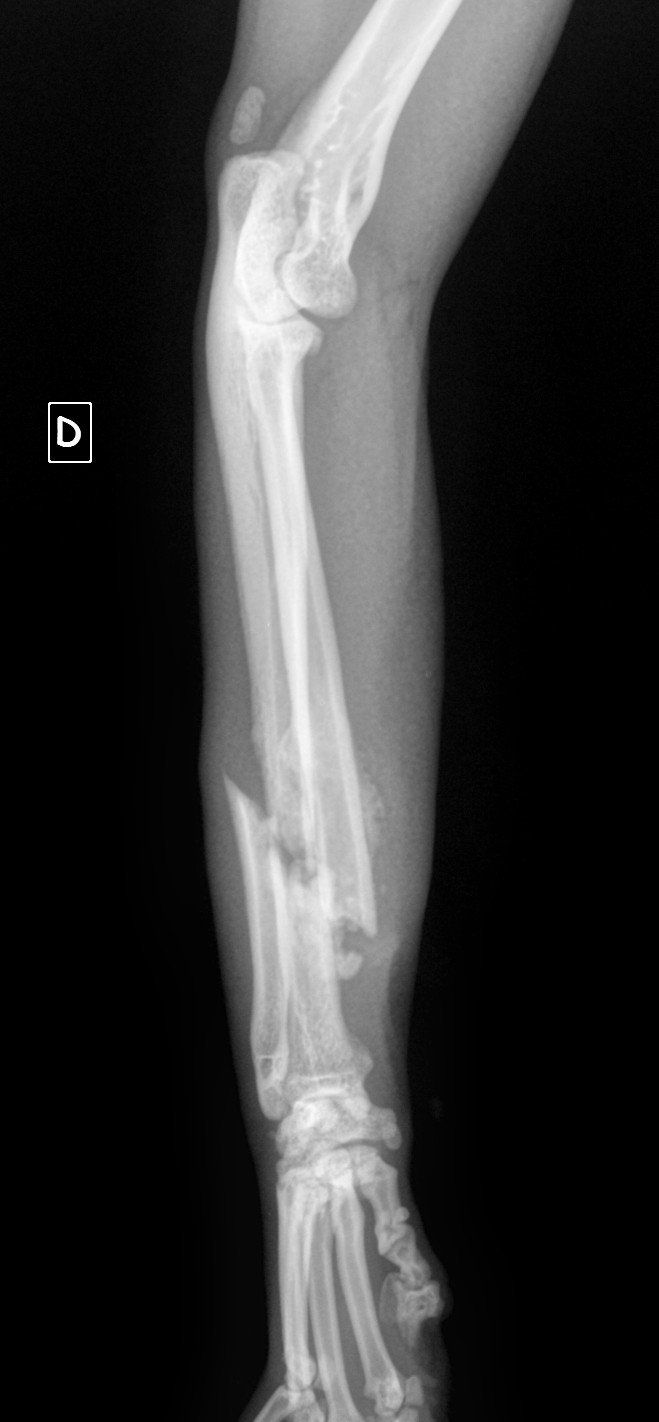

Il a eu le bon réflexe de la déposer chez le vétérinaire du quartier qui a constaté que la petite avait sa patte avant gauche déformée. Il s’est avéré, en grandissant, qu’elle ne se sert pas de sa patte.

Nous l’avons emmené en consultation au CHVA de Beaulieu à Nantes pour avoir l'avis d'un spécialiste. Hélas, il faudra l’amputer car Uanna n’a aucune sensibilité à cette patte. Elle est handicapée et cela devient un fardeau pour elle car Uanna a du mal à se déplacer. Elle s’est blessée plusieurs fois, cela devient urgent pour elle

Tess est une jeune chatte d'à peine un an qui a eu la chance de croiser sur son chemin un certain monsieur, sur la route de Montbert. Elle ne marchait que sur 3 pattes alors ce monsieur l'a déposée dans un cabinet vétérinaire et le verdict tombe : fracture ouverte datant de plusieurs jours. La blessure est telle que l'amputation n'est plus une option... Le cabinet a tenté de retrouver les propriétaires de cette chatte adorable, en vain. Ils ont également contacté plusieurs associations et nous avons répondu présent pour financer cette opération urgente et prendre en charge Tess par la suite. Elle est actuellement en convalescence dans l'une de nos familles d'accueil qui n'a pas hésité une seconde malgré le manque de place ! Elle sera prochainement proposée à l'adoption après sa stérilisation. Nous ne lançons pas d'appel aux dons à chaque opération que nous prenons en charge mais sachez que votre générosité sert à préserver leur vie, à les sauver pour certain et ce fut le cas pour Tess. Merci à ce monsieur de lui être venu en aide et merci aux donateurs sans qui nous ne pourrions continuer nos actions !